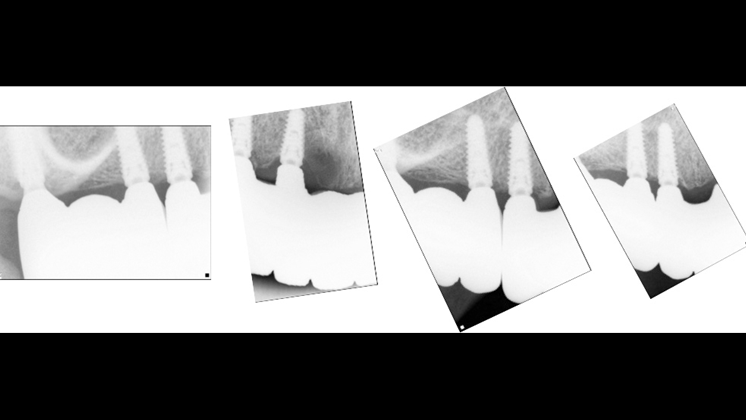

Clinical case: Extraction of all teeth in upper maxilla,

immediate implant placement, & provisionalization

- Courtesy of Dr. Iulian Filipov, Romania -

Keywords

AnyRidge, immediate placement, immediate provisionalization, maxillary fully edentulous case, initial stability, edentulous, Dr. Iulian Filipov, R2GATE, MEGA ISQ

Products:

AnyRidge implant system, Mega ISQ, R2GATE

“AnyRidge ensures long-term biological stability

& functionality even in

full-mouth rehabilitation case. ”